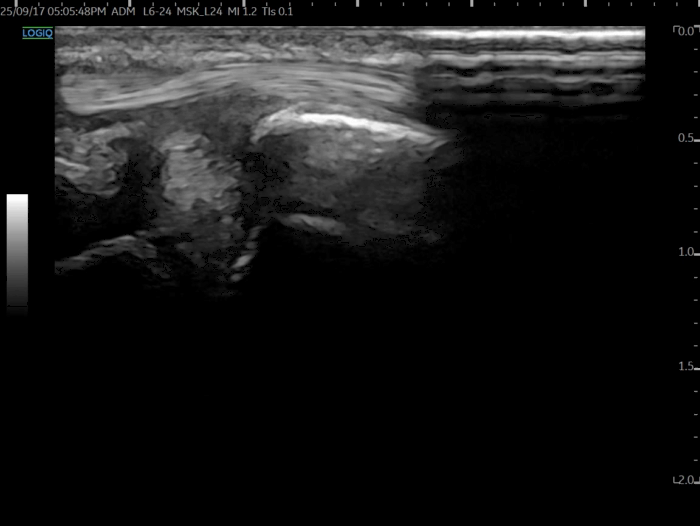

건강한 손목은 새끼손가락 쪽으로 꺾을 때

이 쿠션이 압축되면서 면적이 넓어집니다.

@ https://doi.org/10.3390/s22010345

정상적으로 펴지면서 충격을 흡수하는 거죠.

그런데 TFCC가 손상된 환자들은정반대였습니다.

새끼손가락 쪽으로 꺾을 때

오히려 이 쿠션이 쪼그라들면서

면적이 작아졌습니다.

쿠션이 제 역할을 완전히 잃어버린 겁니다.